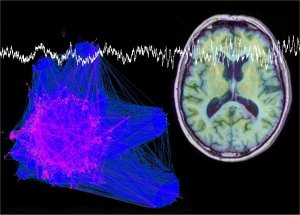

La enfermedad de Alzheimer es una patología neurodegenerativa y de la edad, caracterizada por una pérdida progresiva de la memoria y otros déficits cognitivos, para la que todavía no hay una terapia eficaz. Su incidencia es abrumadora, y su efecto, devastador, en todos los órdenes, ya sea individual, familiar, sanitario como socio-económico. “En la búsqueda de nuevos fármacos para su tratamiento, por tratarse de una patología extremadamente compleja y multifactorial, el diseño de moléculas multipotentes, capaces de actuar simultáneamente en diversos sistemas enzimáticos o receptores implicados en el progreso y desarrollo de la enfermedad, es sin duda una de las estrategias terapéuticas preferidas, adoptada ya en numerosos laboratorios de investigación”, detalla el doctor Marco-Contelles.